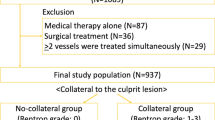

Forty-two patients were recruited for our study between 2011 and 2018 after an elective CCA revealed a CTO. Within 1 month of diagnosis all patients were studied by Cardiac Magnetic Resonance (CMR) using a standard protocol using intravenous contrast agent (Gadovist, Bayer). In conjunction with the patient’s informed consent form, patient history data was obtained using a questionnaire. Questions about smoking, diabetes, hypertension, statins therapy, a positive family history of coronary heart disease, regular exercise and angina pectoris were answered with a yes/no answer option. Late gadolinium enhanced images were obtained 10 min after contrast administration and used for evaluation of myocardial viability defined as less than 50% transmural enhancement. Two of the patients revealed late enhancement patterns suggestive of infiltrative cardiomyopathy. In two patients the re-evaluation of CCA could not confirm a CTO lesion. These four patients were excluded from further analysis with a final number of 38 patients enrolled in the study. The study was approved by the National ethics committee of Slovenia.

Collateral grade

Collateral Grade 0 was found in 10 segments, Grade 1 in 31 segments, Grade 2 in 56 segments and Grade 3 in 123 segments (Table 5)

In addition, scar thickness was classified into dichotomous groups below and including 50% and more than 50% to represent viable and non-viable myocardium, respectively. Our results show that the degree of collaterals is statistically significant higher in the group with scar thickness below and including 50% (mean 2.31 ± 0.78) as compared to the group with scar thickness above 50% (mean 1.98 ± 0.74; p = 0.001) (Fig. 2). The ratio between viable vs. non-viable myocardium was also increased with the degree of collaterals and was found to be significantly different (p = 0.006) between grades of collaterals (Fig. 3).